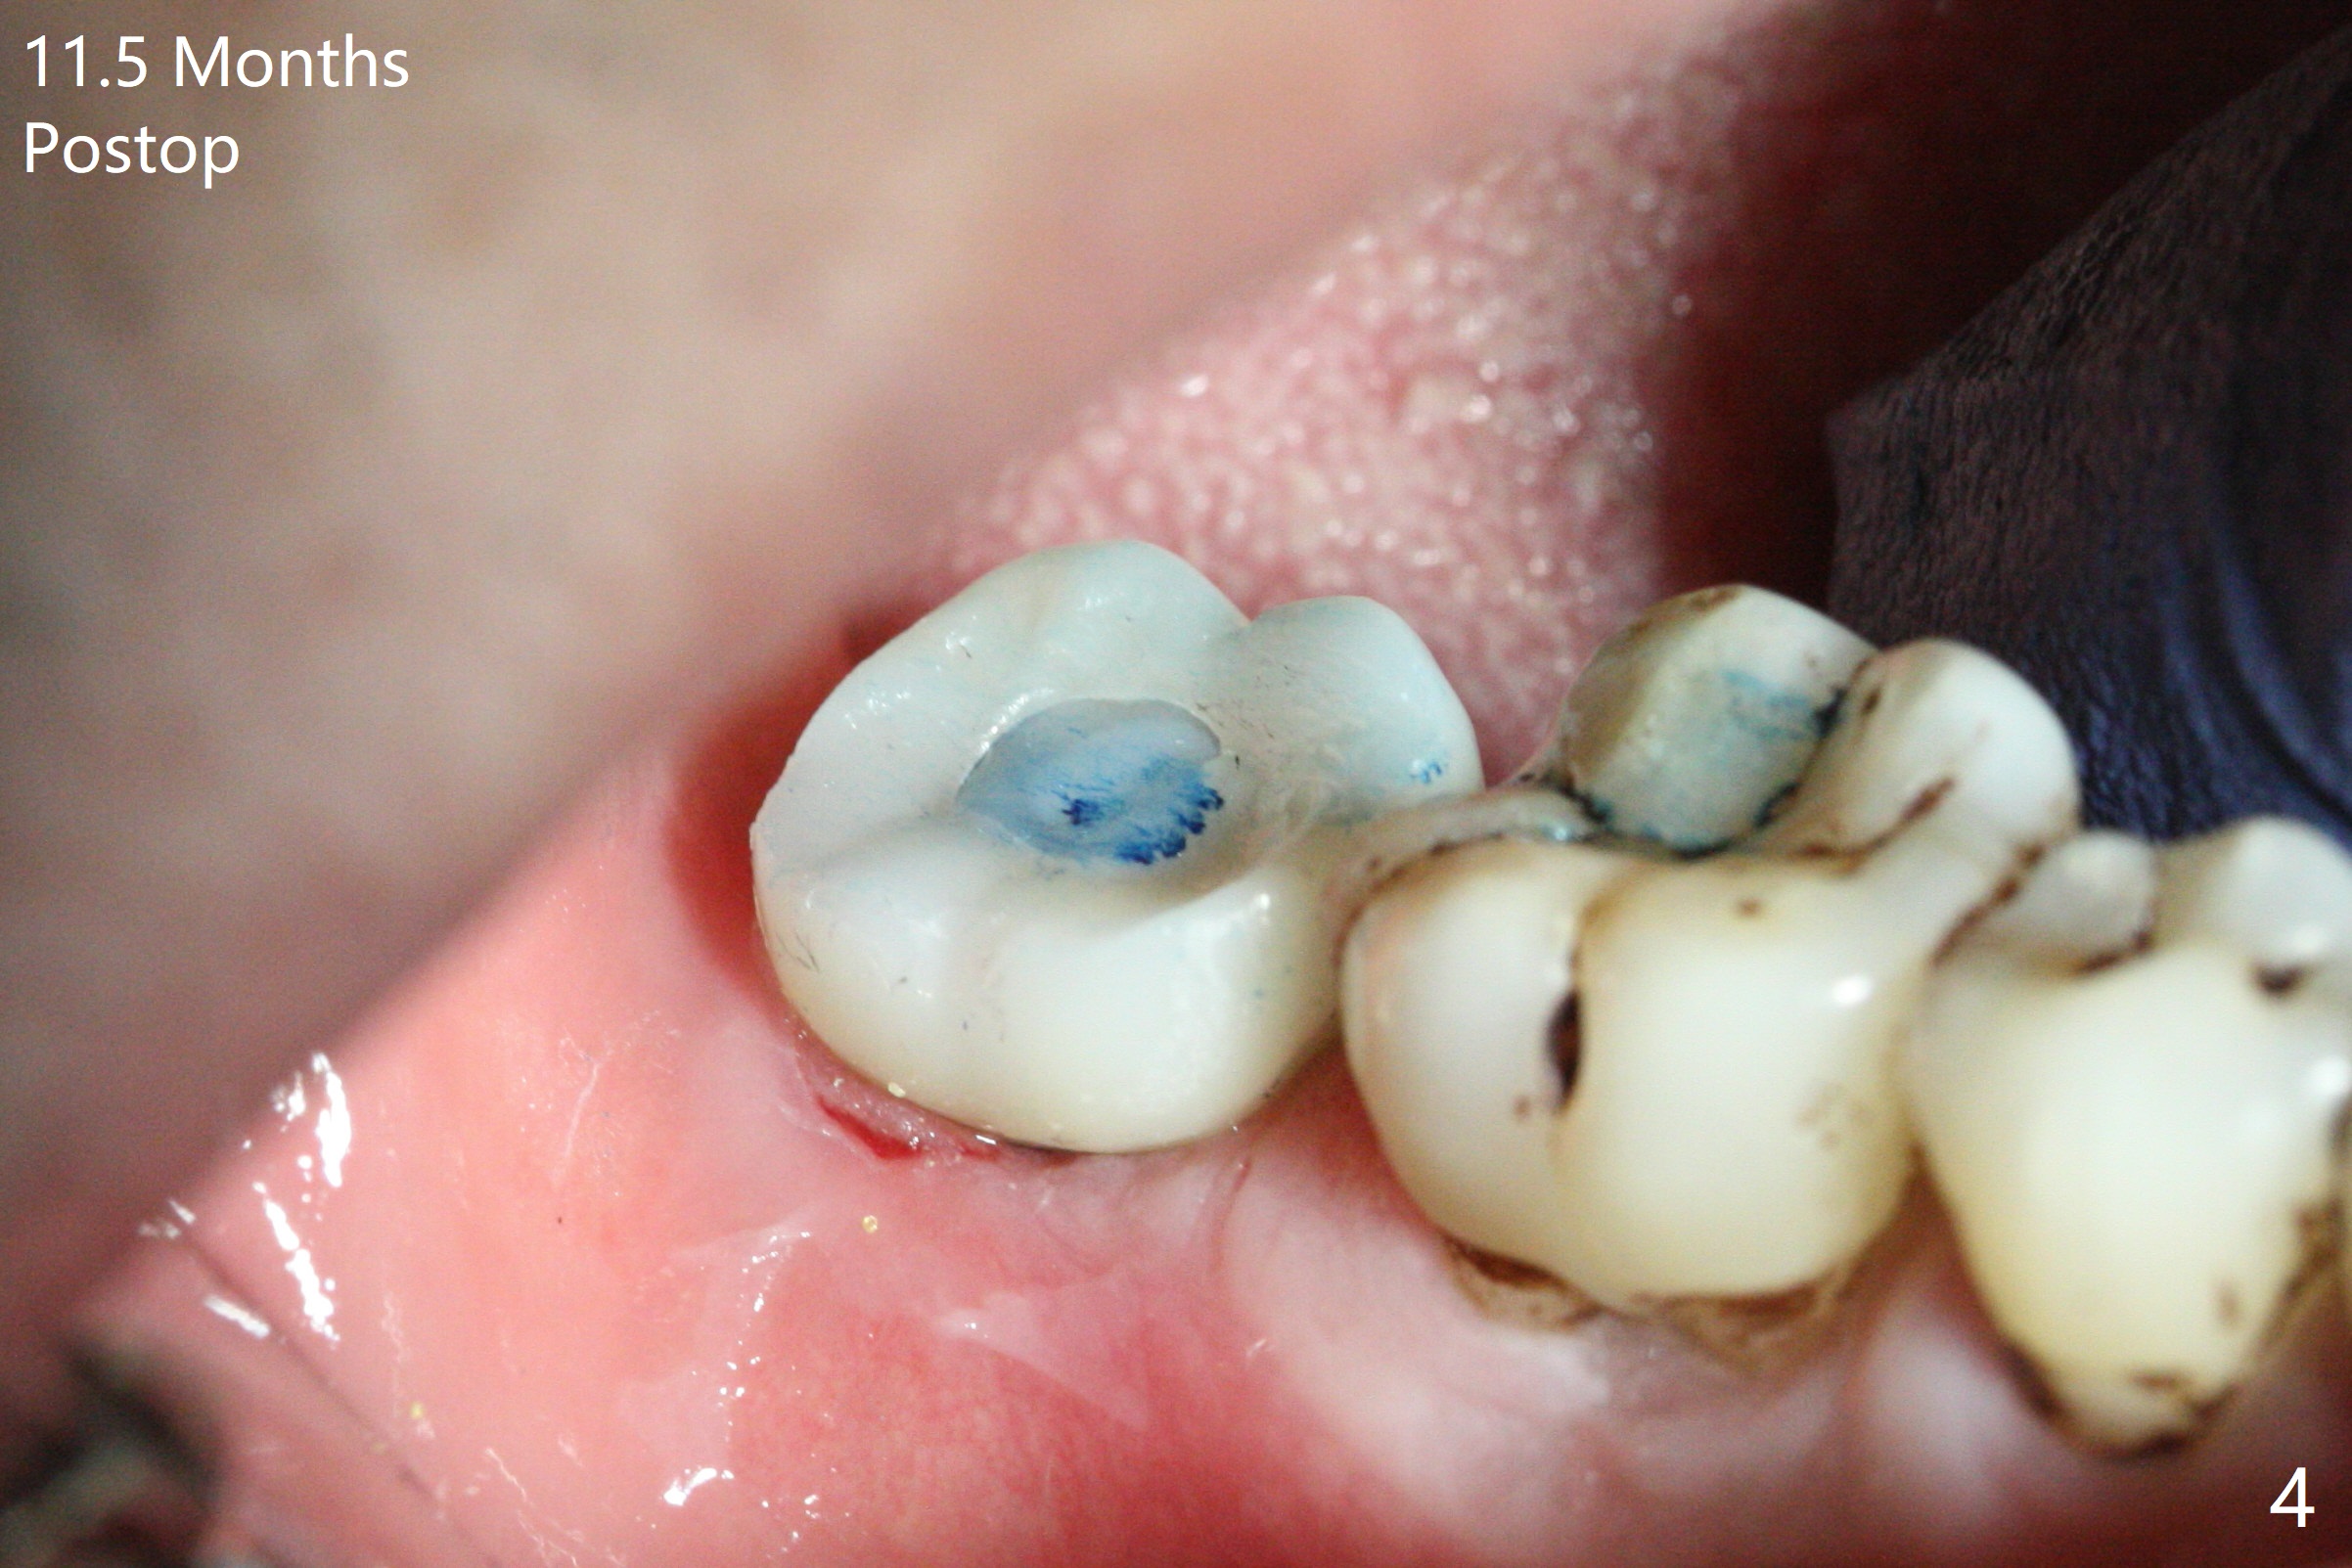

The leukoplakia at the sites of #31 and 32 is most likely related to smoking and the supraerupted teeth #1 and 2 (Fig.0 ^).  After osteotomy for 11.5 mm at #31 (Fig.1), it appears that the bone height is not as much as expected.  The last two drills for sequential osteotomy are 4.3x13 and 4.8x11.5 mm.  A 5x11.5 mm UF implant is placed slightly subcrestal with insertion torque > 50 Ncm (Fig.2).  Following placement of 6.5x2 mm healing abutment, the opposing tooth needs adjustment for height.  Orthodontic intrusion of the opposing tooth is scheduled 2 days later.  It is accidental to find root fracture of the mesial root of the tooth #30 (Fig.1 <).  There is minimal bone resorption coronally 5 months postop (Fig.3).  A provisional is fabricated at #31 to assist in intrusion of the tooth #2.  A crown is cemented 11.5 months postop (Fig.4); the leukoplakia at #31 seems to lessen.  The tooth #30 is lost during the pandemic, followed by looseness of the crown and abutment at #31.  When the complex is reseated, the occlusal scheme is changed, suggesting incomplete seat of the abutment earlier (Fig.5).